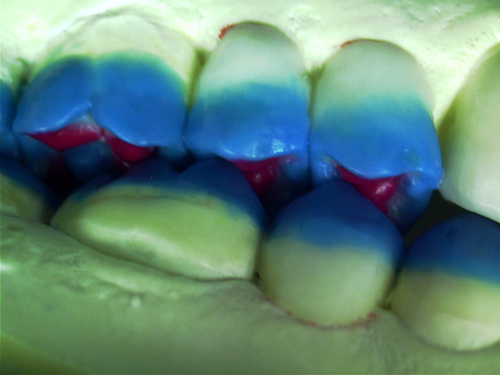

ABSTRACT El Bruxismo es una entidad patológica en la que concurren diferentes factores. Entre ellos el stress que conlleva consigo la vida moderna, constituye el Factor Predisponente sobre el que se ha abundado en innumerables tratamientos de tipo general, actuando sobre la psiquis y el comportamiento del individuo, ya sea con fármacos o bien mediante medios psicológicos. Sin embargo, como tantos desequilibrios provocados por el stress, confluyen siempre con un Factor Desencadenante, que en el caso del Bruxismo se encuentra en las desarmonías entre los componentes varios del Sistema Estomatognático. DESARROLLO Paciente varón, de 43 años, constitución atlética. A la inspección se observan desgastes oclusales que alcanzan la calidad de Facetas Parafuncionales, con dentina expuesta y empastes totalmente gastados y evidentes signos de falta de Disclusión Canina de ambos lados. Sobre dicho montaje se realiza un Encerado Progresivo de Diagnóstico, aportando en el mismo los elementos necesarios para obtener todos los principios básicos de una Oclusión Orgánica. FIG. 6 a 24 Una vez aprobado el fisiologismo de la oclusión en el articulador, se reproducen modelos de yeso con la nueva situación, y se estampa un SET UP en cada maxilar. FIG. 25/26 Procedemos entonces al tallado de las piezas correspondientes a la Guía Anterior, y rebasamos los estampados, creando en boca una nueva situación desoclusiva, que permanece en boca durante los pocos días que transcurren entre la primera y segunda visita de trabajo. FIG. 27/33 Ya abordando en esta segunda visita los sectores posteriores, tanto superiores como inferiores, tallamos siempre de manera supragingival, destacando la importancia vital de la forma obtenida en las provisionales, a las que abrimos plenamente las troneras para lograr una correcta higiene. FIG.34 a 43 FIG. 44 a 52 Efectuados los colados en oro y probados en boca, en el laboratorio se confecciona el bizcochado de la nueva Guía Anterior, la que puede o no copiarse de la Guía Anterior provisional, mediante la técnica denominada Trayectoria Funcionalmente Generada, que consiste en realizar en la platina del articulador un registro estereográfico sobre acrílico Duralay en polimerización. FIG. 57/58 Ajustados todos los detalles mediante esta técnica, se instala en boca en forma Provisional y se deja funcionando una semana o dos, al cabo de las cuales se chequean las disclusiones , los ajustes, la eficacia masticatoria, la carencia de sintomatología articular y muscular. FIG.59 a 63 PIE DE FOTO FIG.9 OBTENCIÓN DE LA GUÍA ANTERIOR FIG.10 Y 11 PITOMBOS. ALINEAC. TRIDIMENSIONAL FIG.12 PITOMBOS. DISCLUSIÓN DER. FIG.13 PITOMBOS. DISCLUSIÓN IZQ. FIG.14 WILSON INF. FIG.15 WILSON SUP. FIG.16 BOCA DE PEZ INF. FIG.17 BOCA DE PEZ SUP. FIG.18 VISTA OCLUSAL FIG.19 O.R.C. FIG.20 DISCLUSIÓN DERECHA FIG.21 CRESTAS TRIANG. INT. FIG.22 CRESTAS TRIANG. INT. FIG.23 CRESTAS TRIANG. INT. FIG 24 CRESTAS TRIANG. INT. FIG.59 DISCLUSIÓN IZQ. FIG.60 DISCLUSION IZQ. FIG.61 DISCLUSIÓN DER. FIG.62 DISCLUSION DER. FIG. 63 AJUSTE PERIFÉRICO